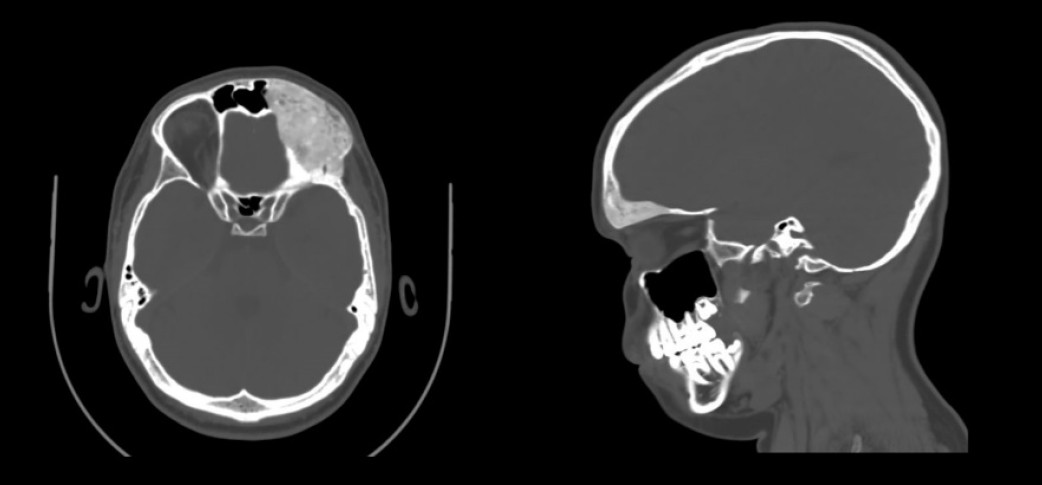

The MSCT imaging revealed affected osseous structure diffuse ill-defined expansible ground glass lesion appearance involving craniofacial region. Notably there was a periosteal thickening along the anterior surface of the left frontal and partial bone. Clinically, a change in the configuration of the face was visualized without pain (Figures 1, 2).

Fig. 1. MSCT (3D cut) showing bony expansion over the left frontal bone region in preoperative stage on 2022

Fig. 2. Preoperative axial computed tomographic image exhibiting characteristic ground-glass opacification of fibrous dysplasia involving the left frontal